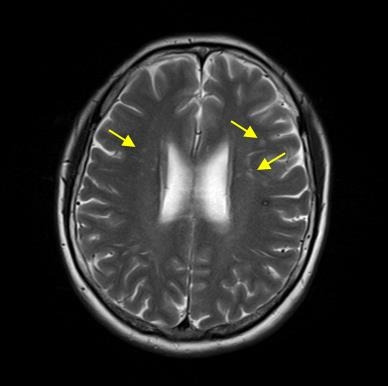

✔ 기능적으로 중요하지 않은(뇌의 활동이 적은) 부위에 뇌졸중이 생기거나 아주 작은 뇌졸중이라면 자각 증상이 없거나 미미할 수 있는데, 이런 경우 뇌 영상 검사를 받다가 우연히 발견하기도 합니다. 이를 흔히 '무증상 뇌경색'이라고 부르며 '무증상 뇌졸증', '열공성 뇌경색' 등으로도 불립니다.

✔ 건강검진 때 뇌 MRI 검사를 하는 사람들이 많아지고 검사 기술도 발전하면서 증상이 없는 뇌혈관질환까지 발견하는 사례가 많이 늘어나며 과거에는 발견할 수 없었던 미세한 이상까지 진단하면서 새롭게 명명된 질환인 셈입니다.